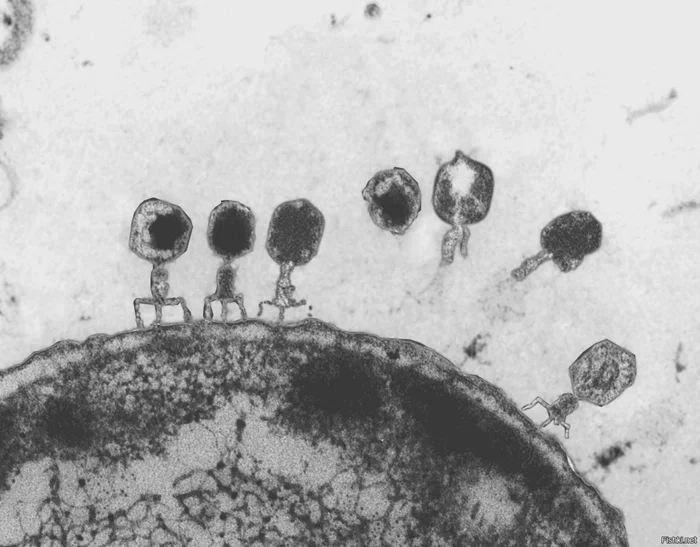

- Использование бактериофагов – это вирусы, которые избирательно уничтожают бактерии.

В отличие от антибиотиков, фаги не трогают полезную микрофлору и не вызывают резистентности. Фаготерапия уже используется для лечения некоторых инфекций, вызванных супербактериями, и показывает высокую эффективность.